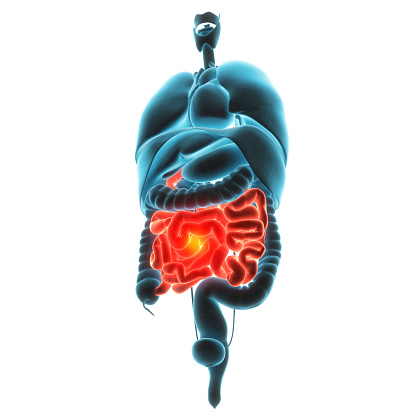

Diverticulitis is a condition that results from the inflammation of diverticula—pouch-like bulges that are found in the lower part of the large intestine. Diverticula in themselves are not harmful and are actually commonly found in adults over the age of 40, but when these pouches become infected, it can lead to the diagnosis of diverticulitis. ...click here to read more